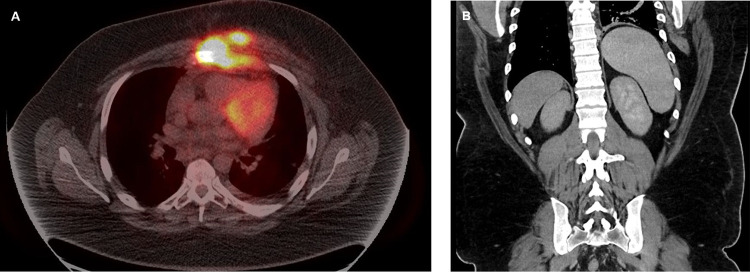

Brentuximab vedotin (BV) and nivolumab are increasingly utilized as a novel regimen in patients with relapsed/refractory classical Hodgkin lymphoma (cHL). A 26-year-old male presented to the hospital with refractory diabetic ketoacidosis and multiple electrolyte abnormalities, 9 days after the first dose of brentuximab vedotin and nivolumab for recurrent classical Hodgkin lymphoma. During his hospitalization, he developed multi-organ failure. His workup showed elevated cytokine levels concerning severe cytokine release syndrome (CRS) and hemophagocytic lymphohistiocytosis (HLH)-like syndrome. Despite treatment with CRS- and HLH-directed therapies, his clinical status deteriorated due to ongoing multifactorial shock and worsening multi-organ dysfunction, and comfort care measures were eventually pursued. To our knowledge, there have been no other cases reported of HLH-like syndrome after the combination of BV and nivolumab in patients with cHL. This case of a fatal adverse event following one dose of BV and nivolumab underscores the vital need for close monitoring of patients receiving this treatment regimen.